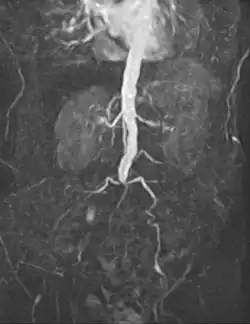

- Abdominal

An abdominal aortic aneurysm (AAA) refers to aneurysmal dilation of the aorta confined to the abdominal cavity. Most commonly, aneurysms are asymptomatic and located in the infrarenal position. Often, they are discovered incidentally or on screening exams in patients with risk factors such as a history of smoking. Patients with aneurysms which have a diameter less than 5 cm are at <1% rupture risk per year. When the aneurysm meets size criteria it can be treated with aortic replacement or EVAR.